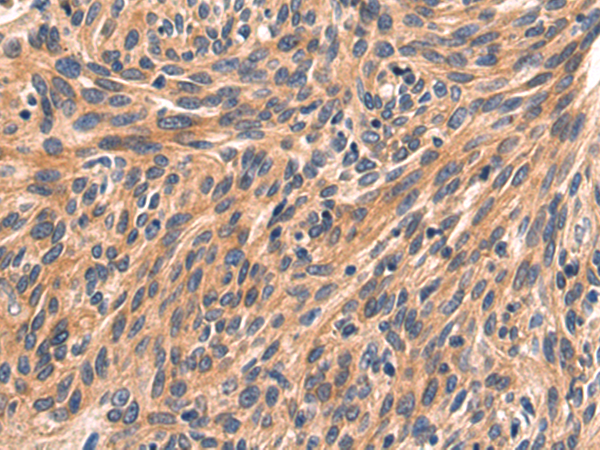

分类: 科研抗体货号: P10727别名: FAD, FACD, FAD1, GLM3, BRCC2, FANCB, FANCD, PNCA2, FANCD1, BROVCA2应用: IHC反应种属: Human